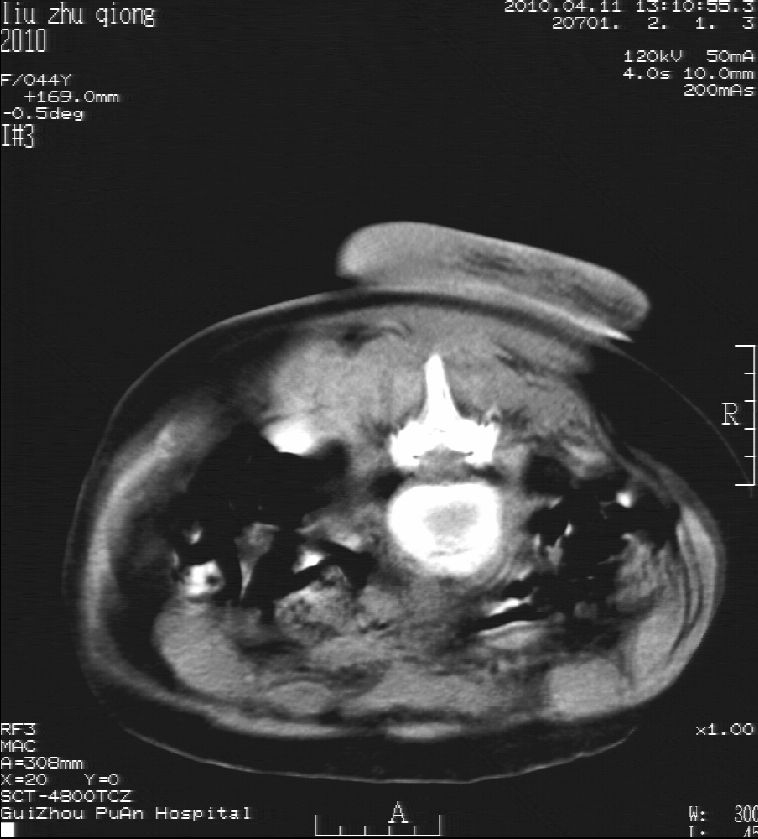

刘某,女,44岁,生第一胎时发现腰背部肿块,黄豆大小,至今17年,呈逐年增大,现行ct检查如下,敬请各位指点。

病史:女,44岁,腰背部肿块,黄豆大小,17年,呈逐年增大。

ct示:骶骨见软组织密度影,似见细条状,或花边状高密度影,考虑不典型钙化灶,向后生长,超出皮肤,可见骶骨破坏,第5幅ct图似与骶管相通。

诊断:脊索瘤

病程长,生长慢,肿块巨大,考虑神经纤维瘤,脂肪密度可以用肿瘤生长过程中包裹入皮下脂肪解释。